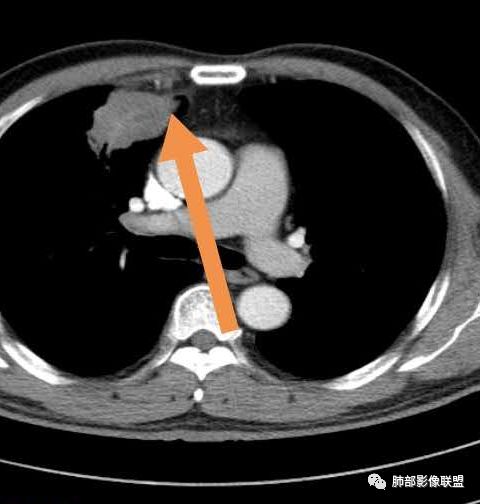

患者,男,52岁主诉:咯血6小时既往史:否认高血压、糖尿病等。定位在哪?

水平裂以上,上叶前段,先看周围,非远端有斑片状高密度影。

边缘平直、稍凹陷,部分区域膨隆。

宽基底与胸膜相连,附近胸膜稍增厚。

支气管进入病灶内,近端堵塞,断端圆钝。

支气管壁均匀稍增厚。

回顾性分析本病例,小编觉得鉴别诊断聚焦于肺鳞癌和炎性病灶(包括结核)之间,这个病灶的炎性征象大于恶性征象;以下是这个病例的的炎性征象:①病灶边缘平直收缩为主,也缺少典型的分叶毛刺;②支气管走行于病灶中央截断,断端比较圆钝;③近端引流支气管壁增厚;④整体强化不显著,坏死区太圆太规整,边缘隐约显示强化的环;⑤血管走形自然,未见明显破坏征象;⑥胸膜外脂肪间隙增宽,胸膜广基地增厚,未见栽赃;⑥52岁偏年轻(此条也不大支持鳞癌)

虽然本例患者支气管截断,病灶中央截断炎性及恶性都可以,断端向病灶一侧圆钝更支持炎性。